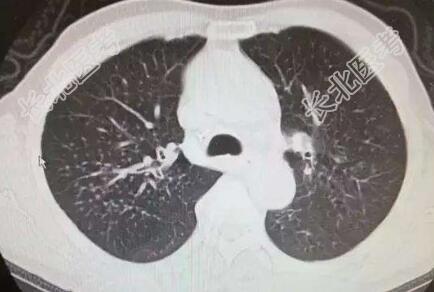

辅助检查:心电图:窦性心律,肺型P波,T波改变;心脏彩超:主动脉瓣退变伴少量返流,左室舒张功能减退;颅脑+胸部+颈部CT:双侧基底节区、丘脑、放射冠多发新陈梗塞灶,老年性脑改变,C3-4C4-5椎间盘突出,C6椎体后缘增生,右上肺结节影。